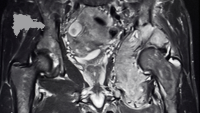

República Dominicana.–Los médicos ortopedas traumatólogos Andy de León y Edwin Suffront aseguran que el volumen de pacientes con actividad neoplásica con tumores a nivel óseo, articular y partes blandas ha aumentado significativamente en el país, después de la pandemia del covid-19. .(Seguir leyendo…)